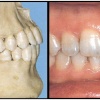

Sügav hambumus või sügav kattumine eesmiste hammaste osas

Normaalse hambumuse puhul katavad ülemised eeshambad alumisi 1/3 krooni pikkuse ulatuses ning alumiste eeshammaste lõikeserv on kontaktis ülemiste lõikehammaste suulaepoolse pinnaga. Sügavhambumuse puhul katavad aga ülemised hambad alumisi lõikehambaid rohkem...